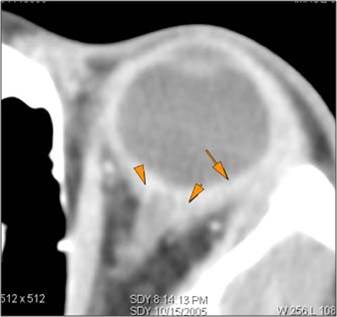

Eyes

Proptosis is present.

The optic nerve is stretched in appearance.

Signs of tension orbit or endophthalmitis are present.